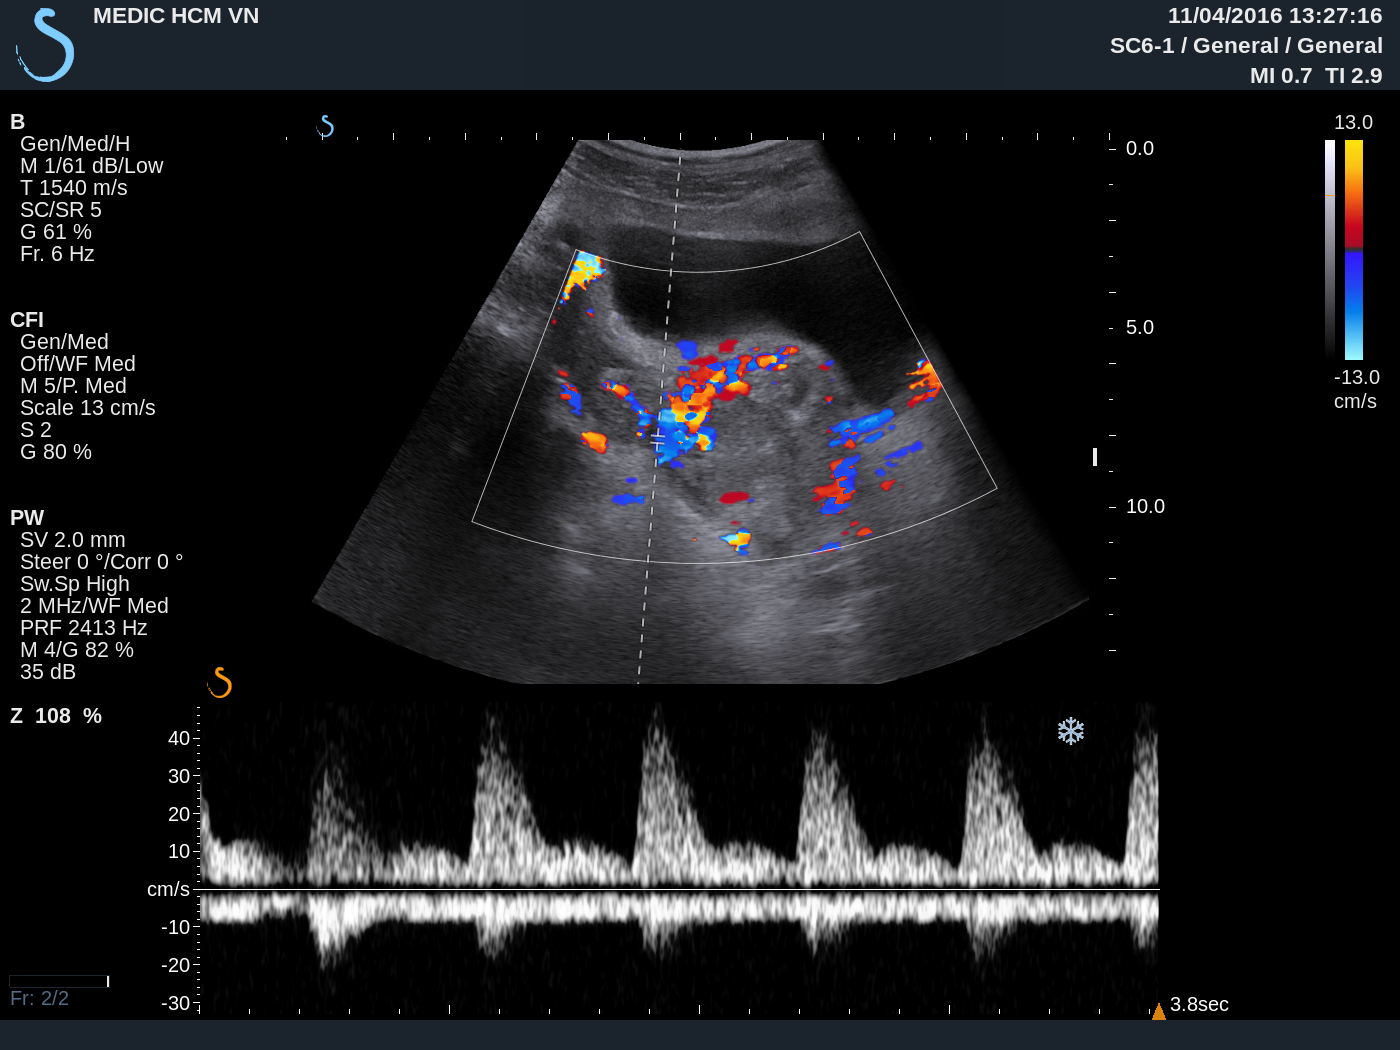

Ultrasound again detected one hypervascular mass at the neck of uterus ( see 3 USimages).

MRI uterusof this mass suspected gestation at neck uterus in the scar of cesarian section before.